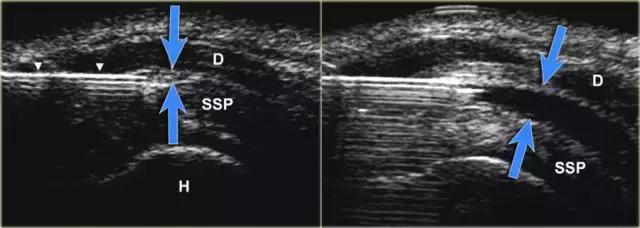

肩峰下滑囊

肩峰下 - 三角肌囊是滑膜内衬空间,其不包含可视察到的或仅很小量的流体。滑囊由两个法氏囊叶组成。 外侧和内侧叶分别与三角肌筋膜和肩袖融合。 滑囊叶可以容易地彼此滑动,从而便于肩部的运动范围。盲性肩峰下注射药物到肩峰下囊中是全科医生和矫形外科医生经常进行的治疗。 错过肩峰下囊肿的注射发生率为12%至70%。